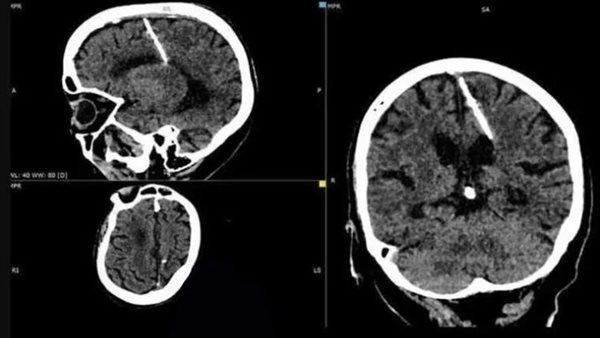

كشفت الآشعة المقطعية لعجوز بالغة من العمر 80 عامًا، من منطقة سخالين الروسية، أن لديها إبرة معدنية مقاس 3 سم مغروزة في الجانب الأيسر من دماغها.

ووفقًا لـ odditycentral، نشرت وزارة الصحة في سخالين مؤخرًا صورًا لنتائج الآشعة المقطعية للمرأة، مع تفسير صادم، حيث يعتقد الأطباء أن الإبرة تم إدخالها إلى دماغها من قبل والديها، بعد وقت قصير من ولادتها، وبقدر ما يبدو ذلك صادما، فإن مثل هذه الممارسات كانت شائعة في روسيا التي مزقتها الحرب.

من غير الواضح كيف نجت المرأة البالغة من العمر 80 عامًا من محاولة قتل والديها، ربما اعتبروا نجاتها معجزة وقرروا أنها كانت كذلك ولكن الأمر الأكثر لفتًا للانتباه هو حقيقة أنها لم تعان أبدًا من صداع شديد، بسبب وجود جسم غريب في دماغها، لولا الآشعة المقطعية الأخيرة، لم تكن لتعرف بوجودها هناك.

وقال الأطباء إن التدخل الجراحي لإزالة الإبرة المعدنية لن يؤدي إلا إلى تعريض المريضة للخطر، نظرا لتقدمها في السن، وخلصوا إلى أن الإبرة لا تشكل خطرا على صحتها وأنها ستستمر في حياتها كما كانت من قبل، وستبقى تحت إشراف طبيبها.